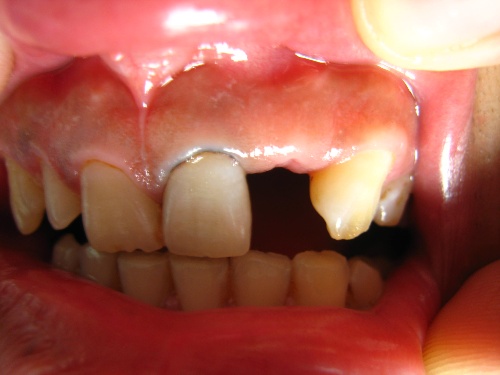

一例固定橋的備牙

一例固定橋的備牙全程圖片介紹

排齦線置入左上1后,

初步備完1

舌側(cè)觀

左上3放入排齦線中

備牙后的情況

再看一張

臨時(shí)冠戴入口內(nèi)的情況

取出模型后的情況